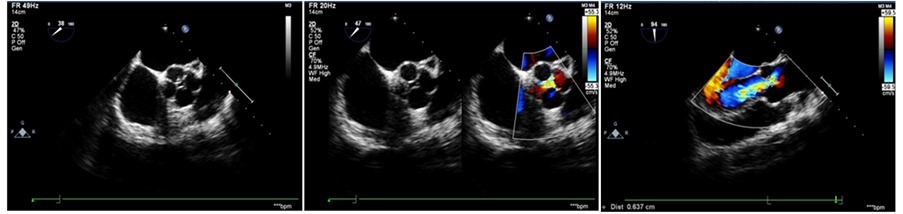

Electrocardiogram showed sinus rhythm with left ventricular hypertrophy by voltage criteria (Figure 1). Two-dimensional (2D) echocardiography showed enlarged left ventricle and established the diagnosis of quadricuspid aortic valve. Short axis image showed aortic valve with four thin cusps of equal size with thickened tips. The cusps formed cruciate closure line in diastole and rectangular shape in systole. Colour Doppler revealed eccentric regurgitant jet occupying more than 50% of left ventricular outflow tract and extending up to the head of papillary muscle. Figure 2 depicts transthoracic color Doppler echocardiography showing QAV with moderate aortic regurgitation. The regurgitant volume was 53 ml/beat, regurgitant fraction was 38%, and regurgitant orifice area was 0.18 cm2. As per recommendations of ACC/AHA, this accounts for the presence of moderate form of aortic regurgitation [10] . The aortic root was not enlarged. Other valves and chambers demonstrated no structural changes and were normal. A computed tomography (CT) chest scan was then requested for better visualization of the aortic valve, which also depicted the presence of quadricuspid aortic valve with four equal sized cusps (Figure 3).

Figure 2. Transthoracic color Doppler echocardiograph showing quadricuspid aortic valve with moderate aortic regurgitation (regurgitant volume: 53 ml/beat).